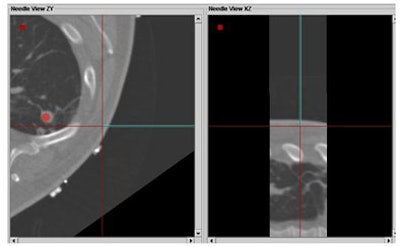

Finally, the researchers compared the results of different aiming methods with the tracking system versus conventional ultrasound/CT guidance. That is, two interventional radiologists did their best to aim the needles based on viewing CT/ultrasound images, versus aiming with the tracking system.

![]() |

| Above, tracking angle for radiofrequency ablation of the lung based on CT/ultrasound guidance versus tracking method (below) yielded better results with automated tracking. |

Based on eight data points in six patients, and with a mean distance from the target of 78 ± 33 mm, the in-plane distance was 2.4 mm ± 1.2 mm with navigation compared to 14.4 mm ± 7.4 with conventional CT/US, and the difference in angles between the two methods was 10.5° ± 2.8°, Krücker said.